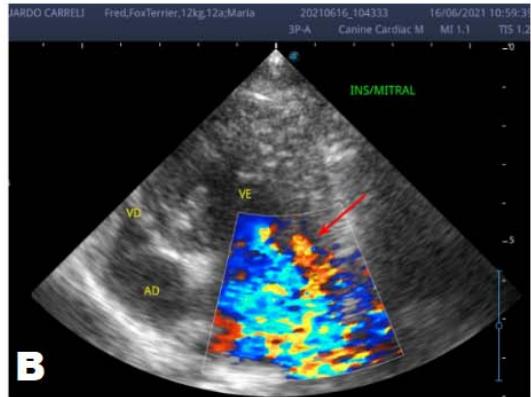

An echocardiogram (ECHO) (Figure 1) showed a thickened mitral valve and enlarged heart chambers. At first was prescribed Pimobendan PO at a dose of $0.25\mathrm{mg/kg}$ BID, continuous use, and requested to return in 30 days.

Figure 1: Echocardiogram 2021: Thickened/degenerated mitral valve (A); Observed in Doppler mode, significant mitral valve insufficiency (B); Hemodynamic assessment - Mitral regurgitation gradient: $3.45 \mathrm{~m} / \mathrm{s} / 47.68 \mathrm{mmHg}$; enlargement of left cardiac chambers; left ventricular diastolic dimension above normal limits was observed

In the reported, he was asymptomatic, and the echocardiographic examination showed enlargement of the left heart chambers, thickened and degenerated mitral valve (Figure 1), left ventricular diastolic dimension above normal limits. with normal systolic function parameters, characterizing systolic dysfunction. The thickening and degeneration of the mitral valve indicates its insufficiency, and the other changes represent diastolic dysfunction.